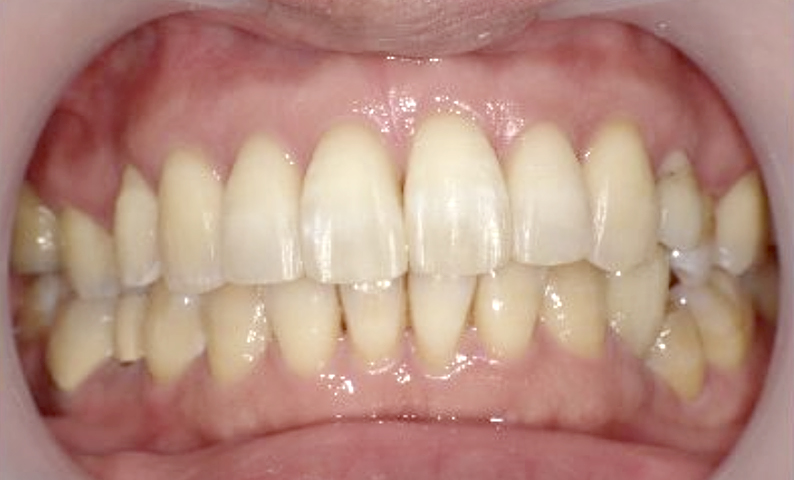

症例_003 下顎だけの部分矯正

治療期間:10ヶ月金額:24万円+税女性前歯のガタガタ下の前歯だけ上顎は補綴治療中

| Before | After |